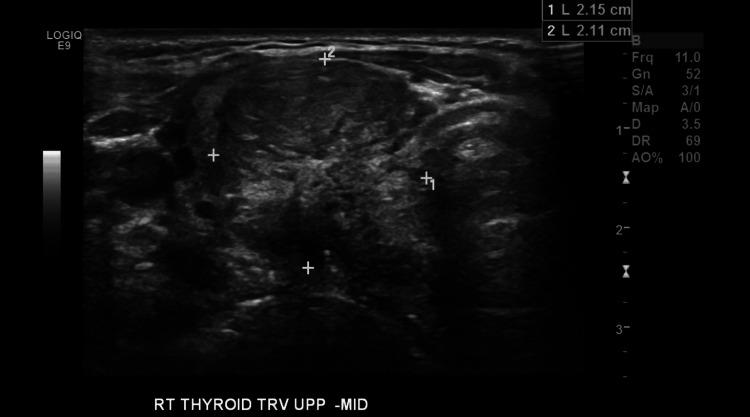

Paragangliomas are abnormal growth cells of neuroectodermal origin that arise from the autonomic nervous system. Head and neck paragangliomas are rare, commonly benign and often have a hereditary origin. Head and neck paragangliomas most commonly arise in the carotid bodies, vagus and glossopharyngeal nerves, and the sympathetic chain. However, we present a case of a paraganglioma arising from the recurrent laryngeal nerve, a phenomenon that has been reported only three times before in the literature. The patient is a 49-year-old female with a past medical history of bilateral carotid body paragangliomas and Hashimoto's disease. She has a family history of paragangliomas in her father and distant relatives and carries a pathogenic variation in the succinate-dehydrogenate subunit D () gene, which was first identified through the original linkage studies involving her family. She presented with a mild swelling sensation in her neck. A thyroid ultrasound revealed a right lobe nodule measuring 3.3 x 2.2 x 2.1 cm. Fine needle aspiration of the nodule revealed an atypia of undetermined significance with a risk of malignancy judged as 50%. A total thyroidectomy was performed due to concern for malignancy. During the operation, the thyroid was nodular and hypervascular. At the right thyroid lobe, there was a pearlescent tubular structure approximately 4-5 mm in size. This was stimulated via intraoperative nerve monitoring and was consistent with being a part of the right recurrent laryngeal nerve. Pathology of the tubular structure revealed a 2.8 cm paraganglioma of the right recurrent laryngeal nerve. An incidental 0.1 cm papillary thyroid microcarcinoma within the left thyroid lobe was also noted. Our patient presented with a history of paragangliomas at a very young age and bilaterality, features that are highly characteristic of hereditary disease. Through the original linkage studies involving her family, her father was recognized as being an obligate carrier at risk of bearing occult paragangliomas. Imaging showed that he carried three paragangliomas. Identification of the familial syndrome as well as testing has now become widely available. Recognizing hereditary paraganglioma and other cancer susceptibility syndromes can help foster more knowledge on the subject and improve clinical outcomes. More attention should be put on the presentation of paragangliomas in an atypical location, such as in our case.